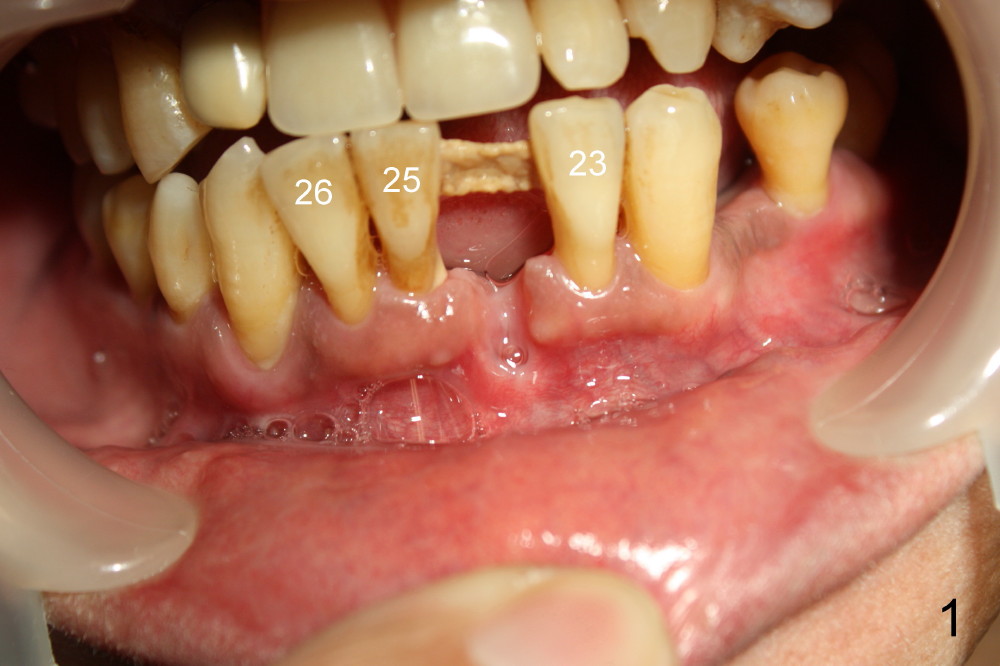

A 51-year-old man has history of periodontitis. The lower incisors have been splinted for several years. He lost a lower central incisor yesterday (Fig.1). The buccal plate of this missing tooth is atrophic. It is planned to have the remaining incisors extracted, place three of one-piece implants (4.0x17 for #23 and 3.5x17 for #25 and 26, Fig.2) and fabricate immediate provisional bridge. Any comments?